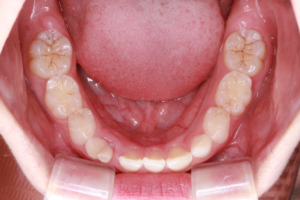

3、臼歯交叉咬合(すれ違い咬合)

・乳歯列期から治療を開始することをおすすめします。

指しゃぶりや口呼吸などによって上顎の歯列が通常に比べて狭くなっている場合、臼歯部の交叉咬合(すれ違い咬合)を引き起こすことがあります。

特に、上下正中線(前歯の真ん中のライン)が顔の真ん中のラインからずれていたり、顎が側方に偏って曲がったようになっている状態の交差咬合の場合、自然に治ることはありません。

骨格性の下顎前突と同じように、成長とともに下顎がさらに偏った状態で発育し、放っておいても症状はどんどん悪化していってしまいます。

そしてそのような交叉咬合は、歯列の変形や顎の不均衡な発育などから顔の変形(非対称)をきたし、将来、顎関節症や顎機能異常の原因となる可能性があります。

乳歯列期は上顎歯列を拡大して正常な顎やお口周りの筋肉の成長発育を促す良い時期でもありますので、この時期に治療をされることが望ましいとされています。

上顎急速拡大を3回行い鼻腔通気が改善しました。

咀嚼指導により、正中が合い、咬み合わせが安定しています。